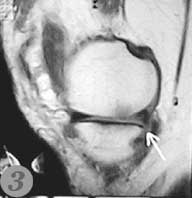

Пример №4 Магнитная томография (МРТ) помогает произвести диагностику сустава до операции

1. повреждение хряща на МРТ